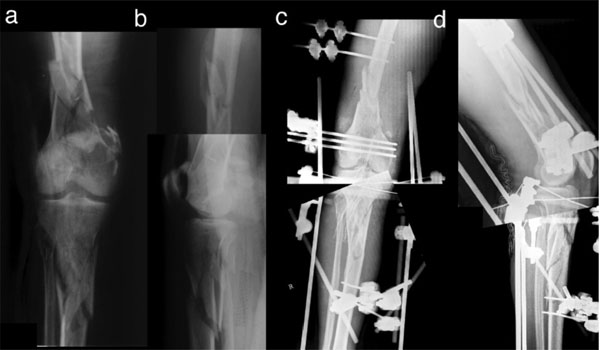

Management of the Floating Knee in Polytrauma Patients Very well made.

Floating Knee Practice Essentials Pathophysiology Etiology Very well made.